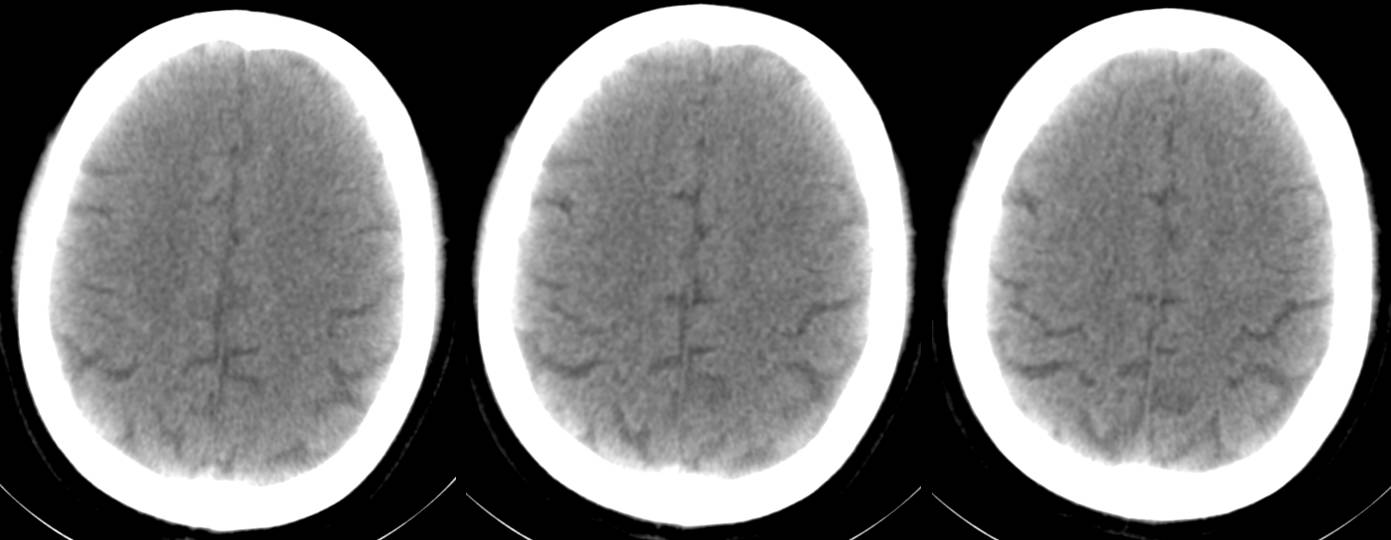

16层CT头部扫描(正常志愿者)